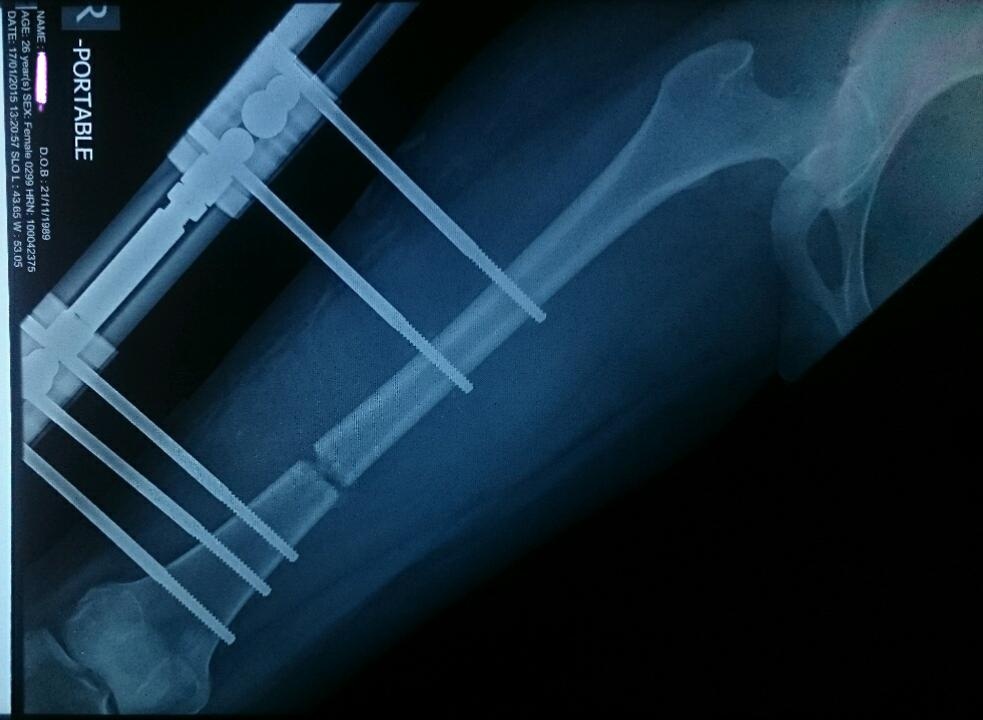

| Quy trình tách xương và ép xương dài ra khiến người thực hiện gặp nhiều đau đớn. Ảnh: Wordpress. |

Trong đó, chân hoặc tay bệnh nhân được tăng chiều dài bằng cách cưỡng ép xương phát triển. cuộc phẫu thuật đầu tiên sẽ làm xương gãy và gắn vòng thép không gỉ vào xương bằng các đinh ghim. Khi xương gãy bắt đầu liền lại, bác sĩ sẽ điều chỉnh để khoảng cách giữa các vòng rộng ra (4 ngày một lần) để ép xương phát triển lấp lại khoảng trống, thường là 1 mm mỗi ngày.

Sau khi quá trình kéo dài hoàn tất, khung thép được giữ nguyên trong giai đoạn củng cố. Bệnh nhân có thể sử dụng nạng để đi lại và trải qua một cuộc phẫu thuật thứ hai để tháo khung. Ngoài ra, họ còn có thể phải phẫu thuật kéo dài dây chằng Achilles để phù hợp với phần xương đã thay đổi. Quy trình đầy đau đớn này được sử dụng cho mục đích trị liệu, nhưng không ít người khỏe mạnh sẵn sàng trải qua những cơn đau để có được chiều cao như ý.